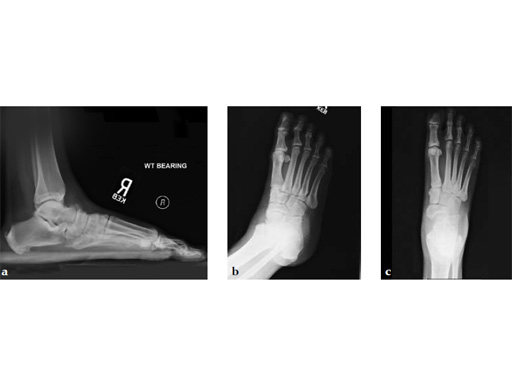

Fusion of the talonavicular joint while saving the rest of the hindfoot complex motion was achieved (see Fig. 4a-c).

The patient returned to work 3 months after surgery. He wears an ankle brace when on uneven surfaces. His lateral column and subtalar pain have resolved.